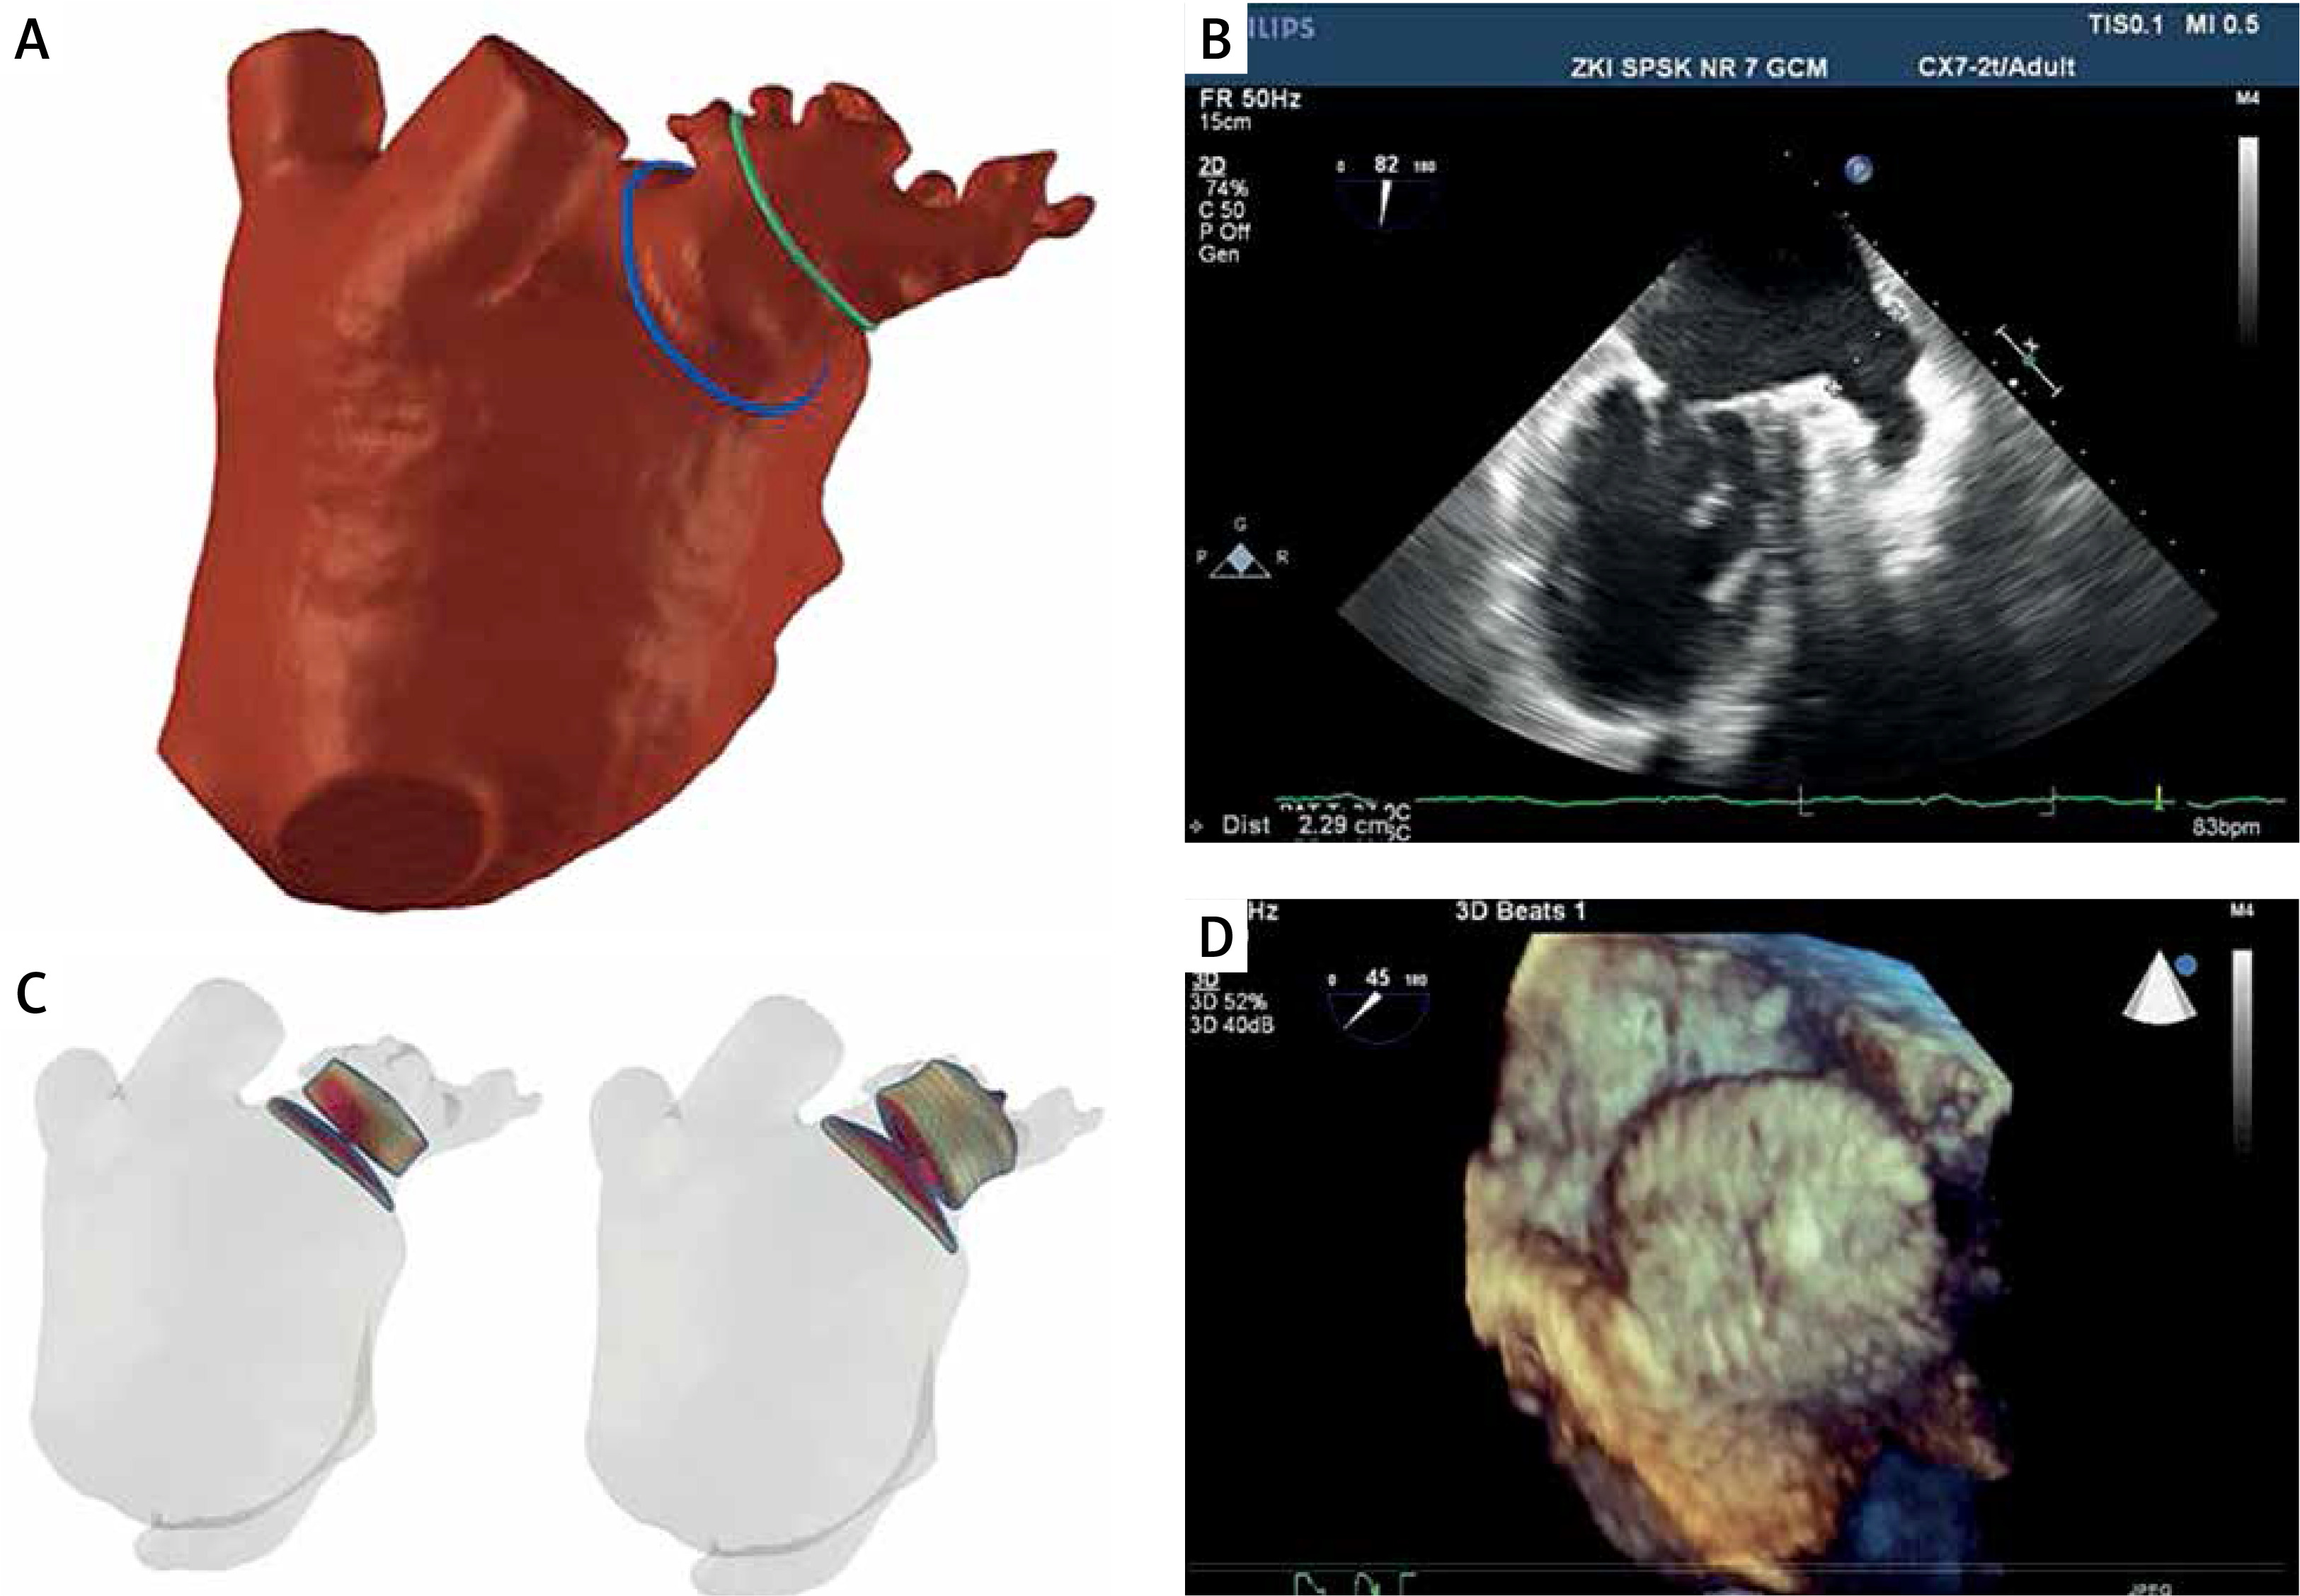

Figure 1

Combined visualization of the appendage using FEops and intraprocedural echocardiography. FEops clearly demonstrates 2-lobed structure (A) with short landing zone. Traditional intraprocedural echocardiography measured landing zone 2.29 cm (B) at the borderline of device sizes 25 and 28 mm. We chose the 25 mm device size based on our preassessment and FEops. The figure shows sample simulation for the 22 mm device with a clear gap in the red color and 25 mm with no gap and proper device deformation (C). We implanted the device with very good sealing (D) and positive follow-up